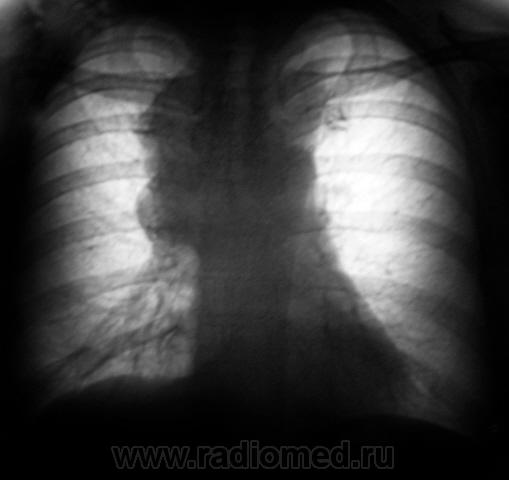

Флюорограмма, ровно через год.

Пациент "взят на контроль".